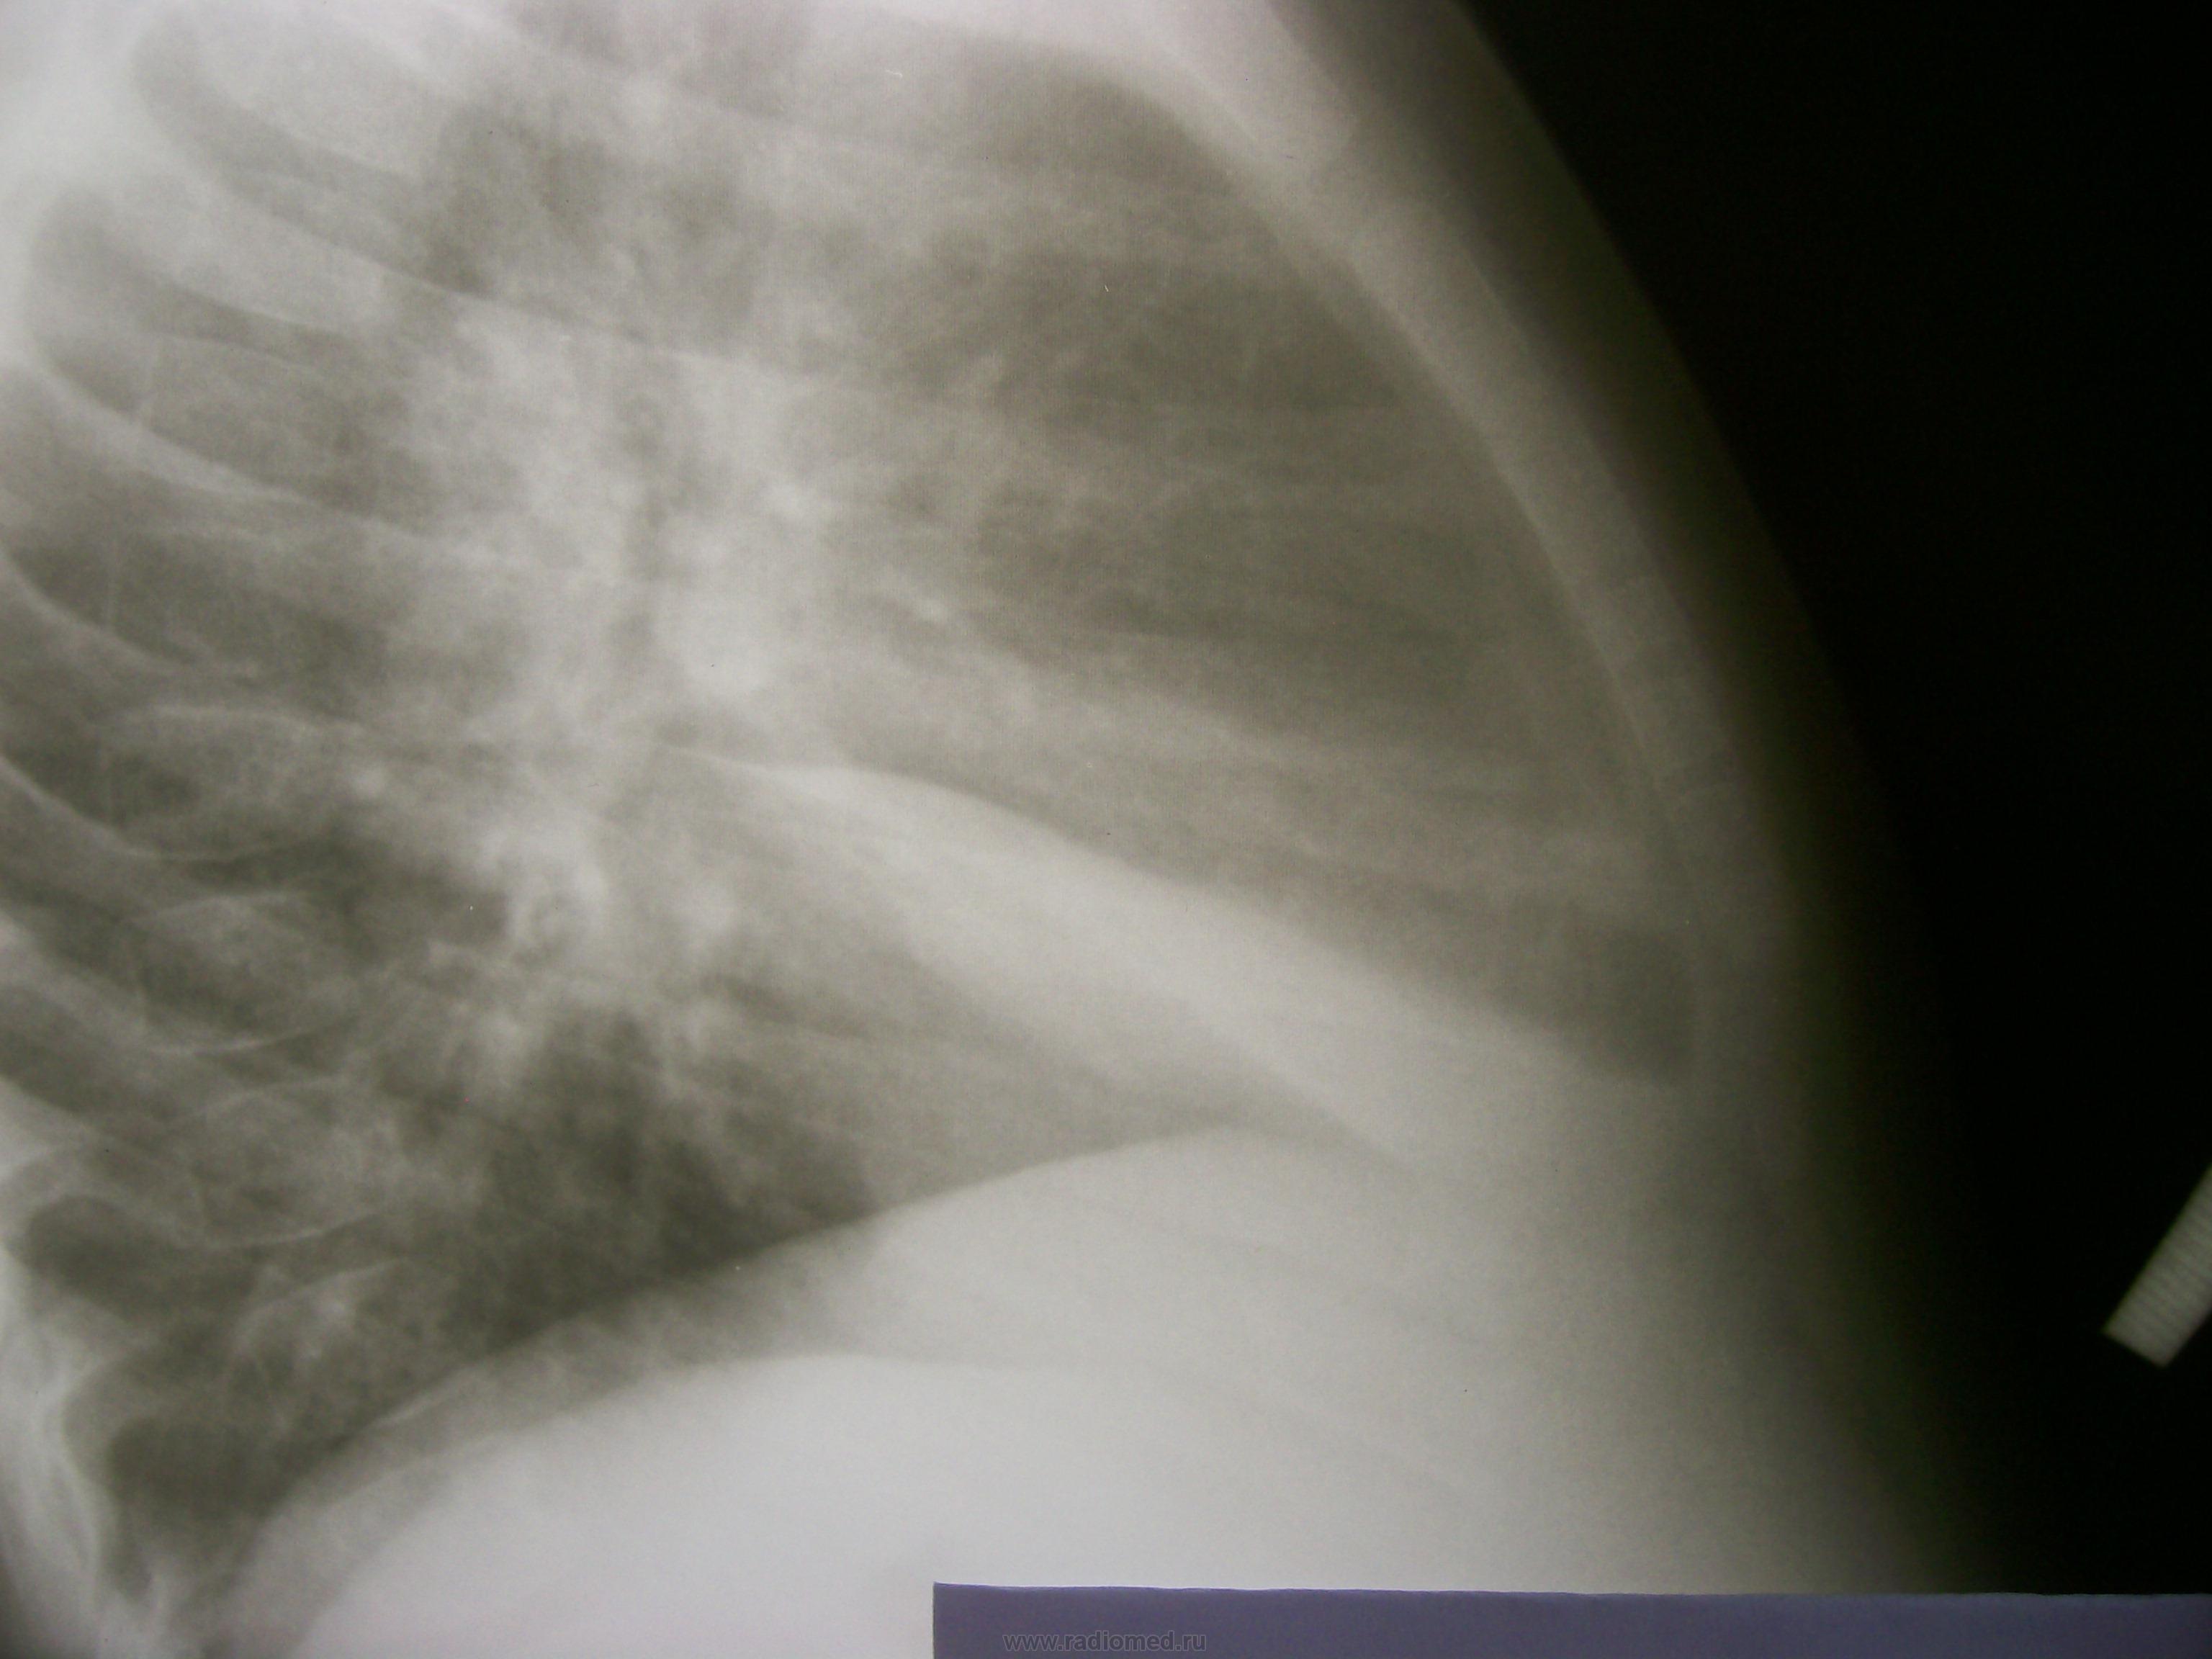

Написал бы р-признаки ателектаза средней доли правого легкого. Если есть возможность, сделал бы снимки по Флейшнеру.

Кстати, видите, как неправильно ограничиваться только прямыми снимками.

Не знаю, есть ли смысл делать по Флейшнеру, гипопневматизация и так видна хорошо. Разве только ради красивой картинки. А вот фтизиатру показать ребенка надо. Изменения идут еще с мая. Некрасивый корень правого легкого, очень вероятно увеличение л/у.

А не аспирация ли здесь, коллеги? Бронхоскопия нужна.

Сейчас ателектаз средней доли. Плюсую к бронхоскопии.

Без сомнений ателектаз. Двухлетнему бронхоскопию? А лечить не пробовали?

Все же не исключал бы неразрешившуюся перициссуральную пневмонию, осложнившуюся междолевым плевритом. Посмотреть ребенка на УЗИ. Сейчас, вроде, в каждом районе есть.